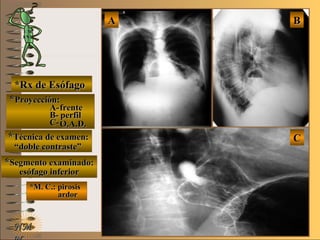

*Rx de Esófago*Rx de Esófago

**Proyección:Proyección:

A-A-

B-B-

C-C-

**Técnica de examen:Técnica de examen:

**Segmento examinado:Segmento examinado:

*M. C.: pirosis*M. C.: pirosis

ardorardor

NMNM

BBAA

CC

frentefrente

perfilperfil

O.A.D.O.A.D.

““doble contraste”doble contraste”

esófago inferioresófago inferior

A-A-El examen es normal o patológico?El examen es normal o patológico?

Examen patológico de esófago inferior con téc-Examen patológico de esófago inferior con téc-

nica de doble contraste en proyección O.A.D. ynica de doble contraste en proyección O.A.D. y

telerradiografía de tórax (frente y perfil)telerradiografía de tórax (frente y perfil)

B-B-La patología es congénita o adquirida?La patología es congénita o adquirida?

Patología adquiridaPatología adquirida

C-C- Dicha patología es orgánica, funcional o mixta?Dicha patología es orgánica, funcional o mixta?

**OpciónOpción

de volverde volver

a ver lasa ver las

imágenesimágenes

Patología adquirida orgánicaPatología adquirida orgánica

D-D-La misma es neoplásica o no neoplásica?La misma es neoplásica o no neoplásica?

Patología adquirida orgánica no neoplásicaPatología adquirida orgánica no neoplásica

E-E-Puede describir la o las imágenes patológicas?Puede describir la o las imágenes patológicas?

Se evidencia en el tórax un nivel hidroaereo re-Se evidencia en el tórax un nivel hidroaereo re-

trocardíaco, que en el examen contrastado detrocardíaco, que en el examen contrastado de

esófago se corrobora como una hernia hiatalesófago se corrobora como una hernia hiatal

parcialmente reductible y con reflujo gastro-parcialmente reductible y con reflujo gastro-

esofágicoesofágico

**Opción avanzada para volver a ver las imágenes con reparosOpción avanzada para volver a ver las imágenes con reparosNMNM

A- frenteA- frente

B- perfilB- perfil

C- O.A.D.C- O.A.D.

nivel hidroaereonivel hidroaereo

esófagoesófago

uniónunión

gástricagástrica

diafragmadiafragma

herniahernia

volvervolver

detalledetalle

stent post-stent post-

quirurgicoquirurgico